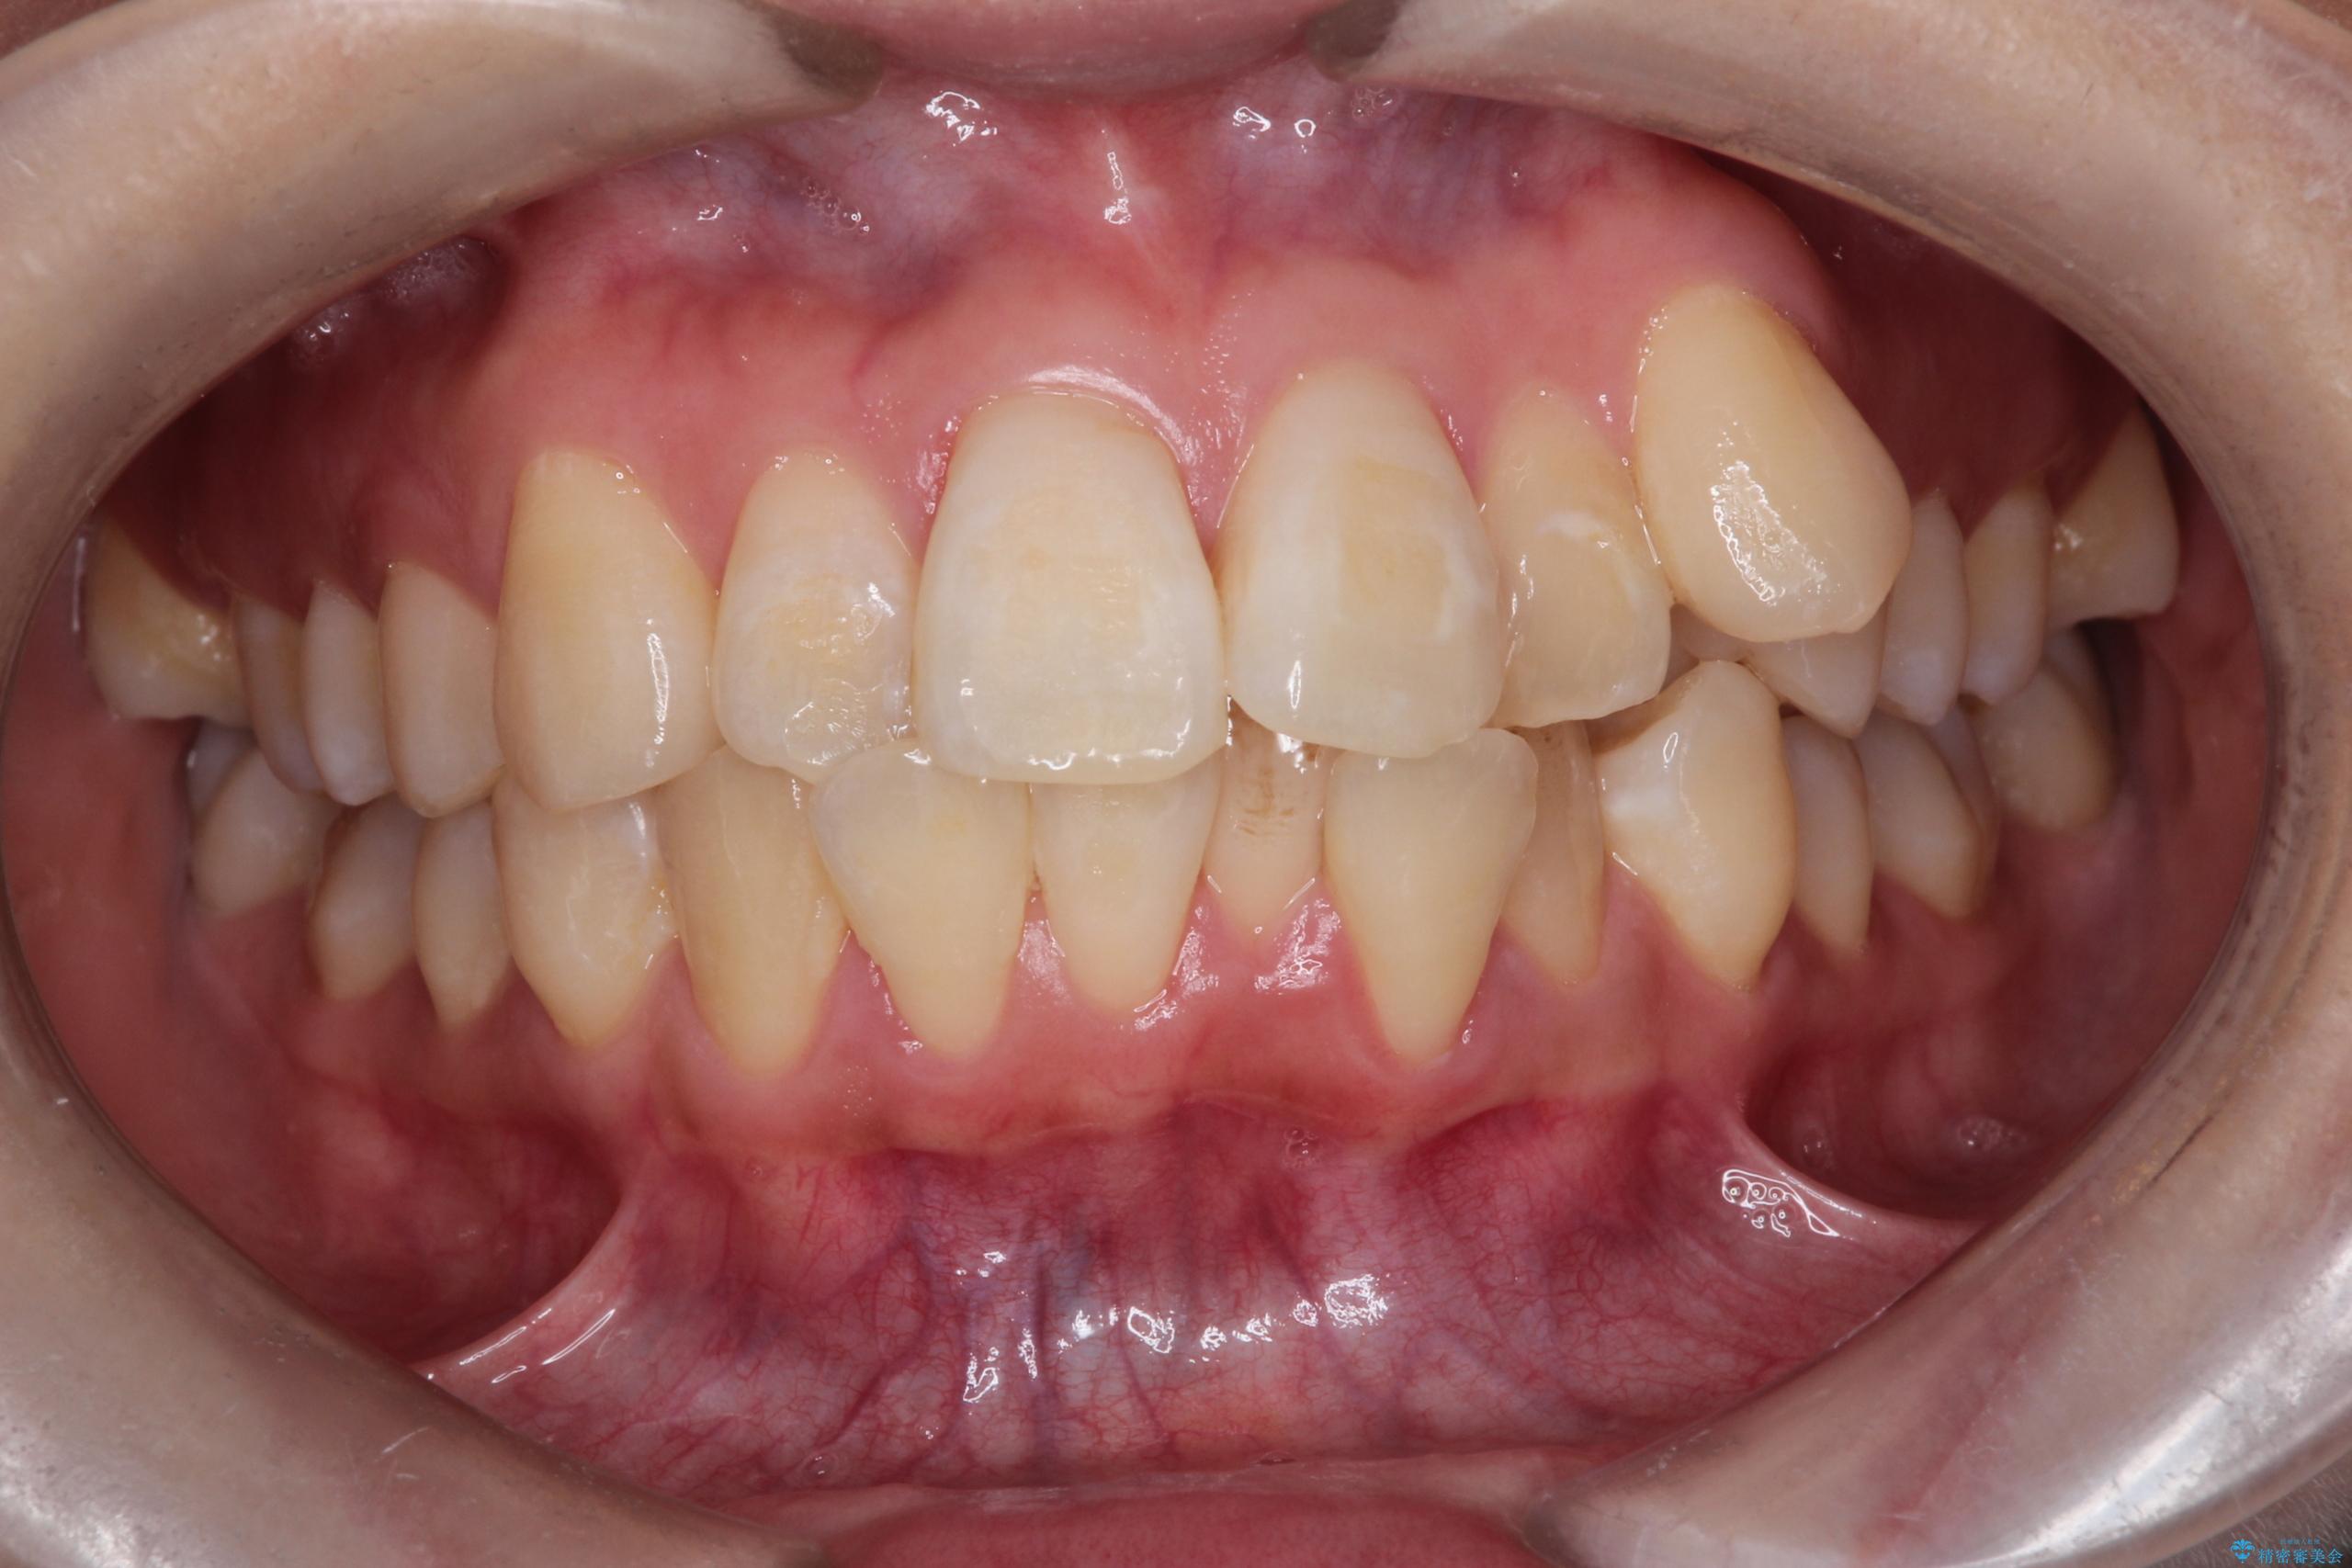

正中のズレ: 歯を左右対称に移動させることで、上下の歯の中心線を正確に合わせ、顔全体のバランスも改善しました。

治療の結果、長年気にされていた八重歯と正中のズレが解消し、機能的にも整った理想的な歯並びを獲得。目立たない装置で治療を完遂し、自信を持って笑える美しい笑顔を手に入れていただけました。